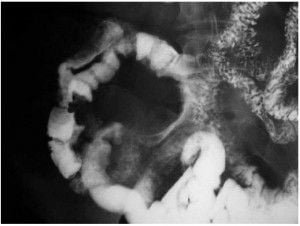

Abdomen, aparato digestivo y via biliarTécnicas de Exploración Radiológica Tránsito del intestino delgado Parte II 28 junio, 2012 Tidito Transito intestinal contraste simple Transito intestinal doble contraste yeyuno e ileon Patologia de Transito intestinal – Enfermedad celiaca Tumor maligno ileon terminalEnfermedad inflamatoria intestinal